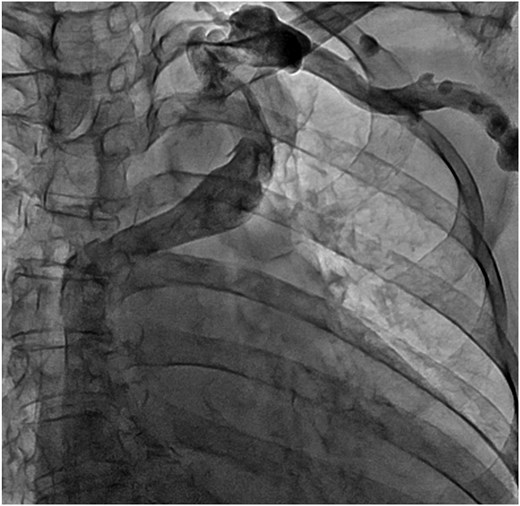

We approached using a median sternotomy and inserted a cannula into the ascending aorta, a 22 Fr right angle cannula directly into the SVC and a 28 Fr straight cannula into the inferior vena cava. The ALBCV was exposed from the left side of the ascending aorta and prepared for potential cannulation. The dorsal side of the ascending aorta was dissected from the right side, confirming ALBCV joined the SVC (Fig. 4 and Video 4). The cannula tip in the SVC did not extend beyond the ALBCV junction. Extracorporeal circulation flow rate was maintained at 2.6 L/min/m2, requiring no additional ALBCV cannula.

Photograph of the surgeon’s view. The left double-dotted line indicates ALBCV. The right double-dotted line indicates the right pulmonary artery. Ao, aorta; RA, right atrium.